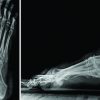

A 50-year-old man with a history of alcoholism was admitted to an emergency hospital, complaining of worsening pain and redness of the right elbow. There was a history of trivial trauma 2 days before this complaint. The X-ray of the elbow was negative, and the patient was discharged with non-steroidal anti-inflammatory drugs (NSAIDs). The day after, the patient returned to the same emergency department because of the persistent erythema and tenderness around his elbow with no systemic inflammatory symptoms. On examination, a skin erythema, edema, warmness, and tenderness were detected on the right elbow, with no axillar lymphadenopathy. The rest of the physical examination was unremarkable. Results of laboratory tests included a white blood cell count of 7770/μL (normal 4000-10000), CRP 533.6 mg/L (0–5), hemoglobin 14.8 g/dL (13–17), glucose 0.83 g/L (0.75–1), creatine 1.4 mg/dL (0.7–1.2), and sodium 133 mmol/L (135–145) with a LRINEC score of 6. Kidney and liver function tests were normal, and a blood culture was negative. The diagnose of cellulitis was evoked and the patient was empirically treated with intravenous antibiotics (Cefazoline 4 g daily and Metronidazole 1500 mg daily). After 5 days, his condition continued to deteriorate with intense pain and significant edema and tenderness of his right elbow. A wound culture revealed a Streptococcus pyogenes infection. Over the course of 6 days, he was brought to our hospital for a surgical advice. On admission to our hospital, the patient was febrile (38°C) and his blood pressure was 148/83 mmHg. Laboratory analysis indicated a white blood cell count of 16000/μL (normal 4000–10000), a CRP 95 mg/L (0–5) and a LRINEC score of 3. Blood endotoxin was negative. The margins of tenderness and erythema spread all over the right upper extremity including the upper right thorax with phlyctens and areas of necrosis (Fig. 1). An emergency aggressive debridement of necrotic tissues was performed, under general anesthesia; after 7 days from his first visit at the emergency room (Fig. 2).